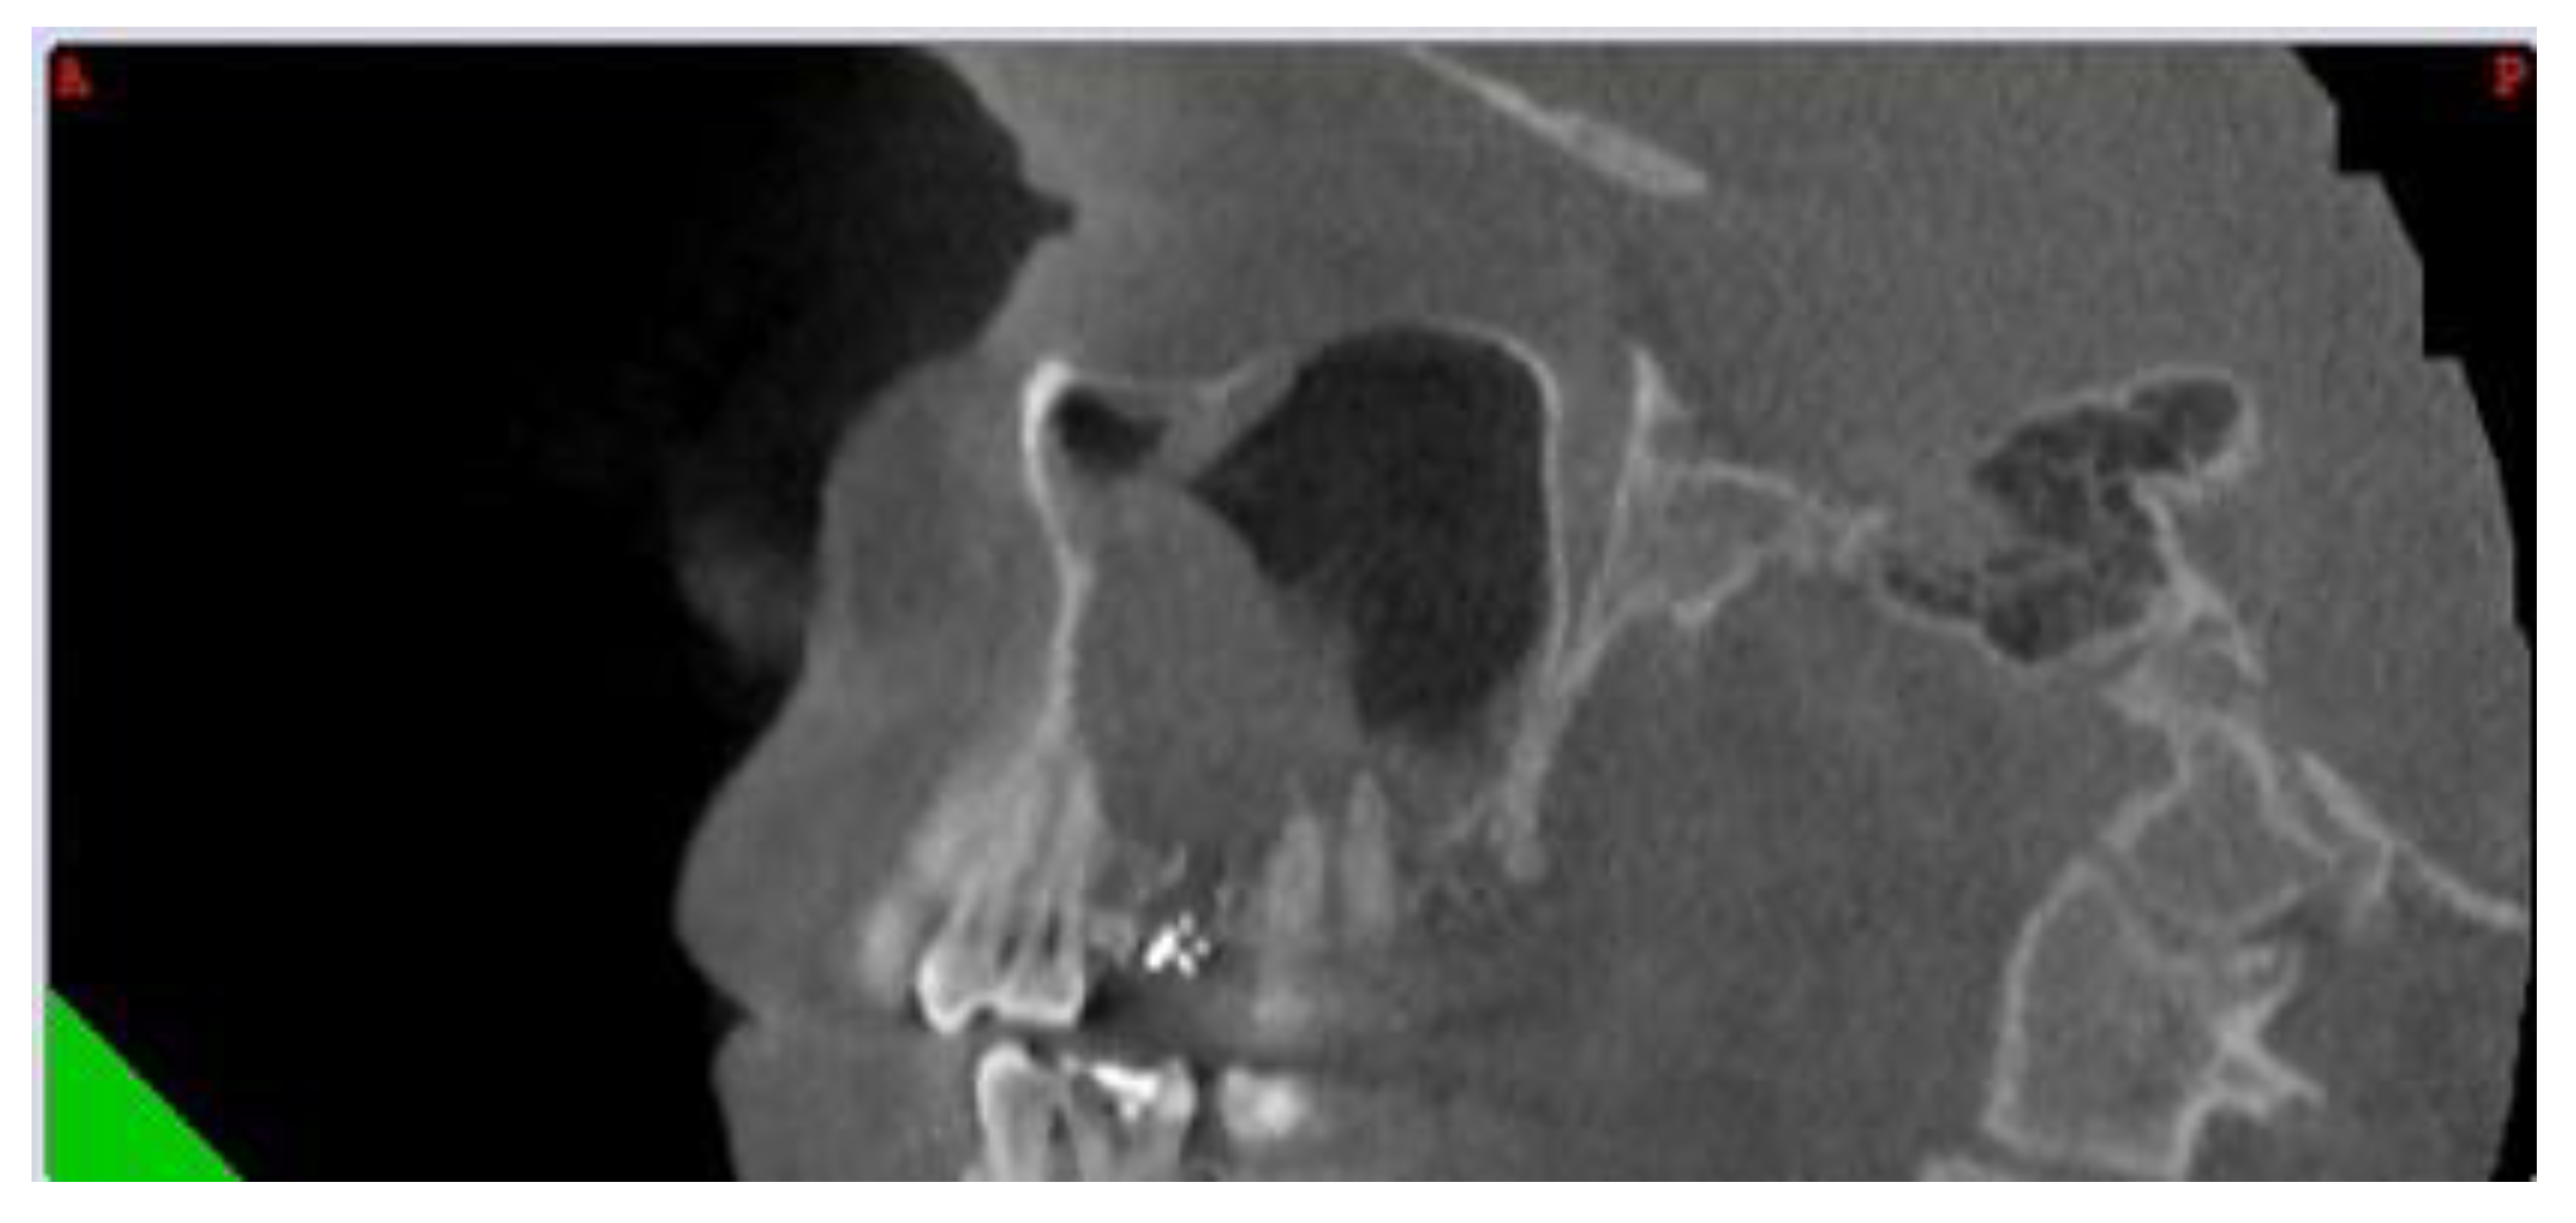

Figure 3.

Sagittal CBCT of a patient with left odontogenic sinusitis and periapical fistula located at the level of the first molar, marked with a white asterix).